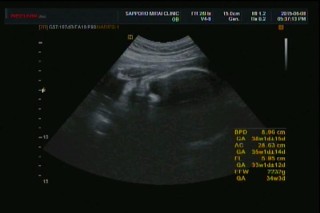

1591gと小さめの女の子です。頭は82.2mmで33w1d相当なんですが、体重は30w6d相当で、足は51.4mmで28w5d相当です。今まで小さめながらも全体的に順調に成長していたんですが、ここで足だけ成長が送れ頭だけ成長が伸びました。2週間後がどうなっているのかすごく気になります。